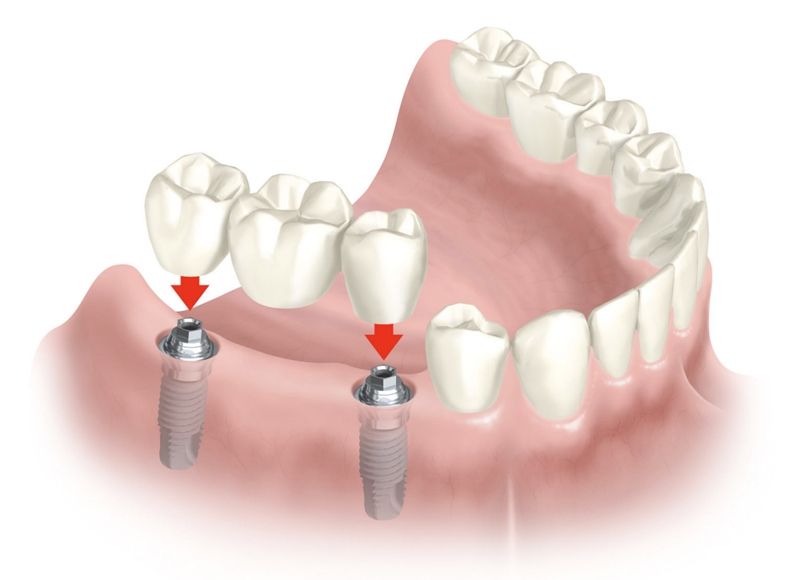

Implante dentário é formado por um cilindro (pino) de titânio, que é inserido dentro do osso, abaixo da gengiva. O tamanho do cilindro varia entre 3 e 6 mm de diâmetro. O titânio, metal biologicamente compatível que se integra perfeitamente ao osso, tem a peculiaridade de impedir qualquer tipo de rejeição óssea. Dessa forma, o implante dentário faz o papel da raiz do dente. Sobre os implantes é que são colocadas as próteses em metalocerâmica, que é o material mais semelhante ao dente natural.